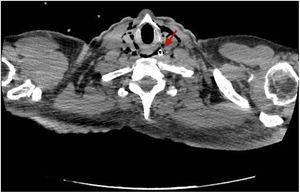

The patient is a 46-year-old male with a history of multiple abdominal surgeries who was admitted for intestinal obstruction. A nasogastric tube (NGT) was inserted, which was initially not productive. Due to clinical worsening, a thoracoabdominal computed tomography (CT) scan was requested, which revealed the extraluminal pathway of the NGT in the abdomen and thorax (Fig. 1); however, no perforation point was observed, and the perforation point was suspected at the cervical level (Fig. 2). ENT examination identified the perforation in the inferior cavum, dissecting the posterior wall of the pharynx. The NGT was withdrawn, and medical treatment was initiated with corticosteroids, fluconazole, and meropenem. The patient presented radiological clinical improvement and began oral tolerance after one week.